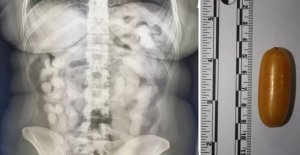

Odmah je bila sumnjiva: Ovo je rendgen Brazilke ko... Brazilka (28) u Zagreb je stigla letom iz Sao Paula preko Lisabona. Bila je sumnjiva pa su joj rendgenom snimili abdomen. Odmah su je prebacili u bolnicu. U sebi je imala čak 76 kapsula s drogom